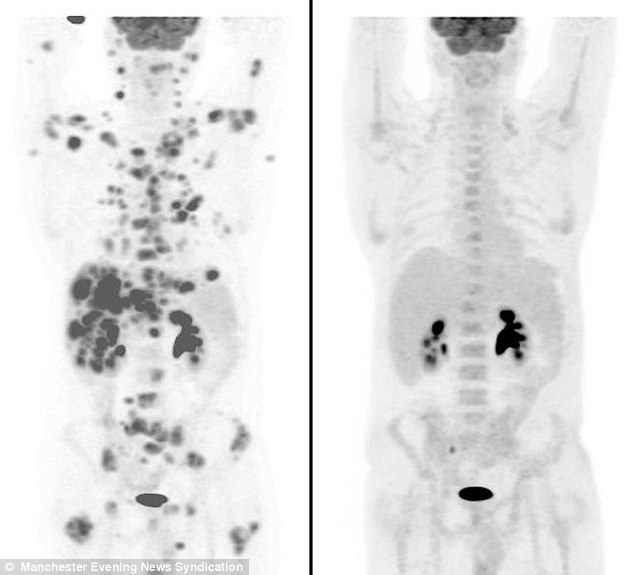

Egy 47 éves súlyos rákbeteg férfi szervezetéből mintegy 70 tumor tűnt el. Ian Brooks ezt az eredményt egy új kísérleti jellegű kezelésnek köszönheti.

A Brentiximab Vedotin segítségével alig 12 hét al...